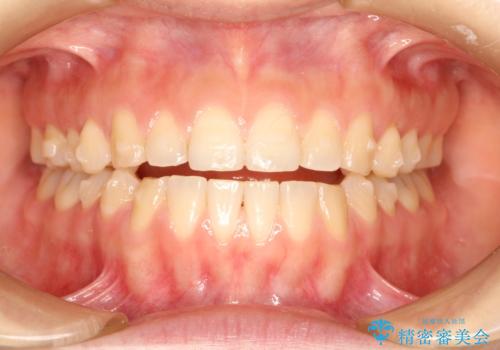

上下の前歯が当たらない インビザラインによる開咬の矯正治療

- 上下の前歯の間に隙間があるとのことで来院されました。

開咬とよばれる、奥歯しか上下の歯が接触していない状態でした。

インビザラインにて矯正治療を行うこととなりました。

使用時間を守っていただけたので、比較的スムーズに矯正を終了することができました。

前歯で物が咬み切れるようになり、喜んでいただけました。